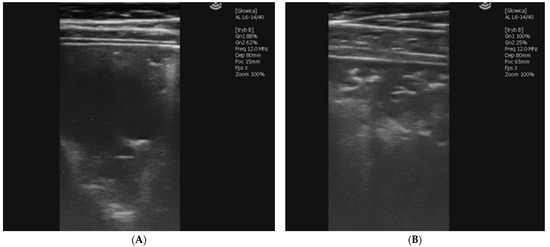

2.1.5. Case 3—Suspicion of Extrapulmonary Disorders